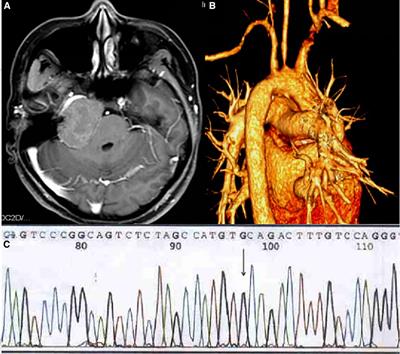

Treatment of Familial Hypercholesterolemia with Intracranial Xanthoma: Case Report

Department of Neurosurgery, West China Hospital, Si chuan University Chengdu, China Intracranial xanthoma is a rare benign intracranial tumor. It often occurs in patients with hyperlipidemia. Intracranial xanthomas grow slowly,...

Relevance: Intracranial xanthoma is a rare benign intracranial tumor. It often occurs in patients with hyperlipidemia. Intracranial xanthomas grow slowly, and clinical symptoms only appear when the mass compresses the surrounding tissues, so early diagnosis of the disease is difficult.